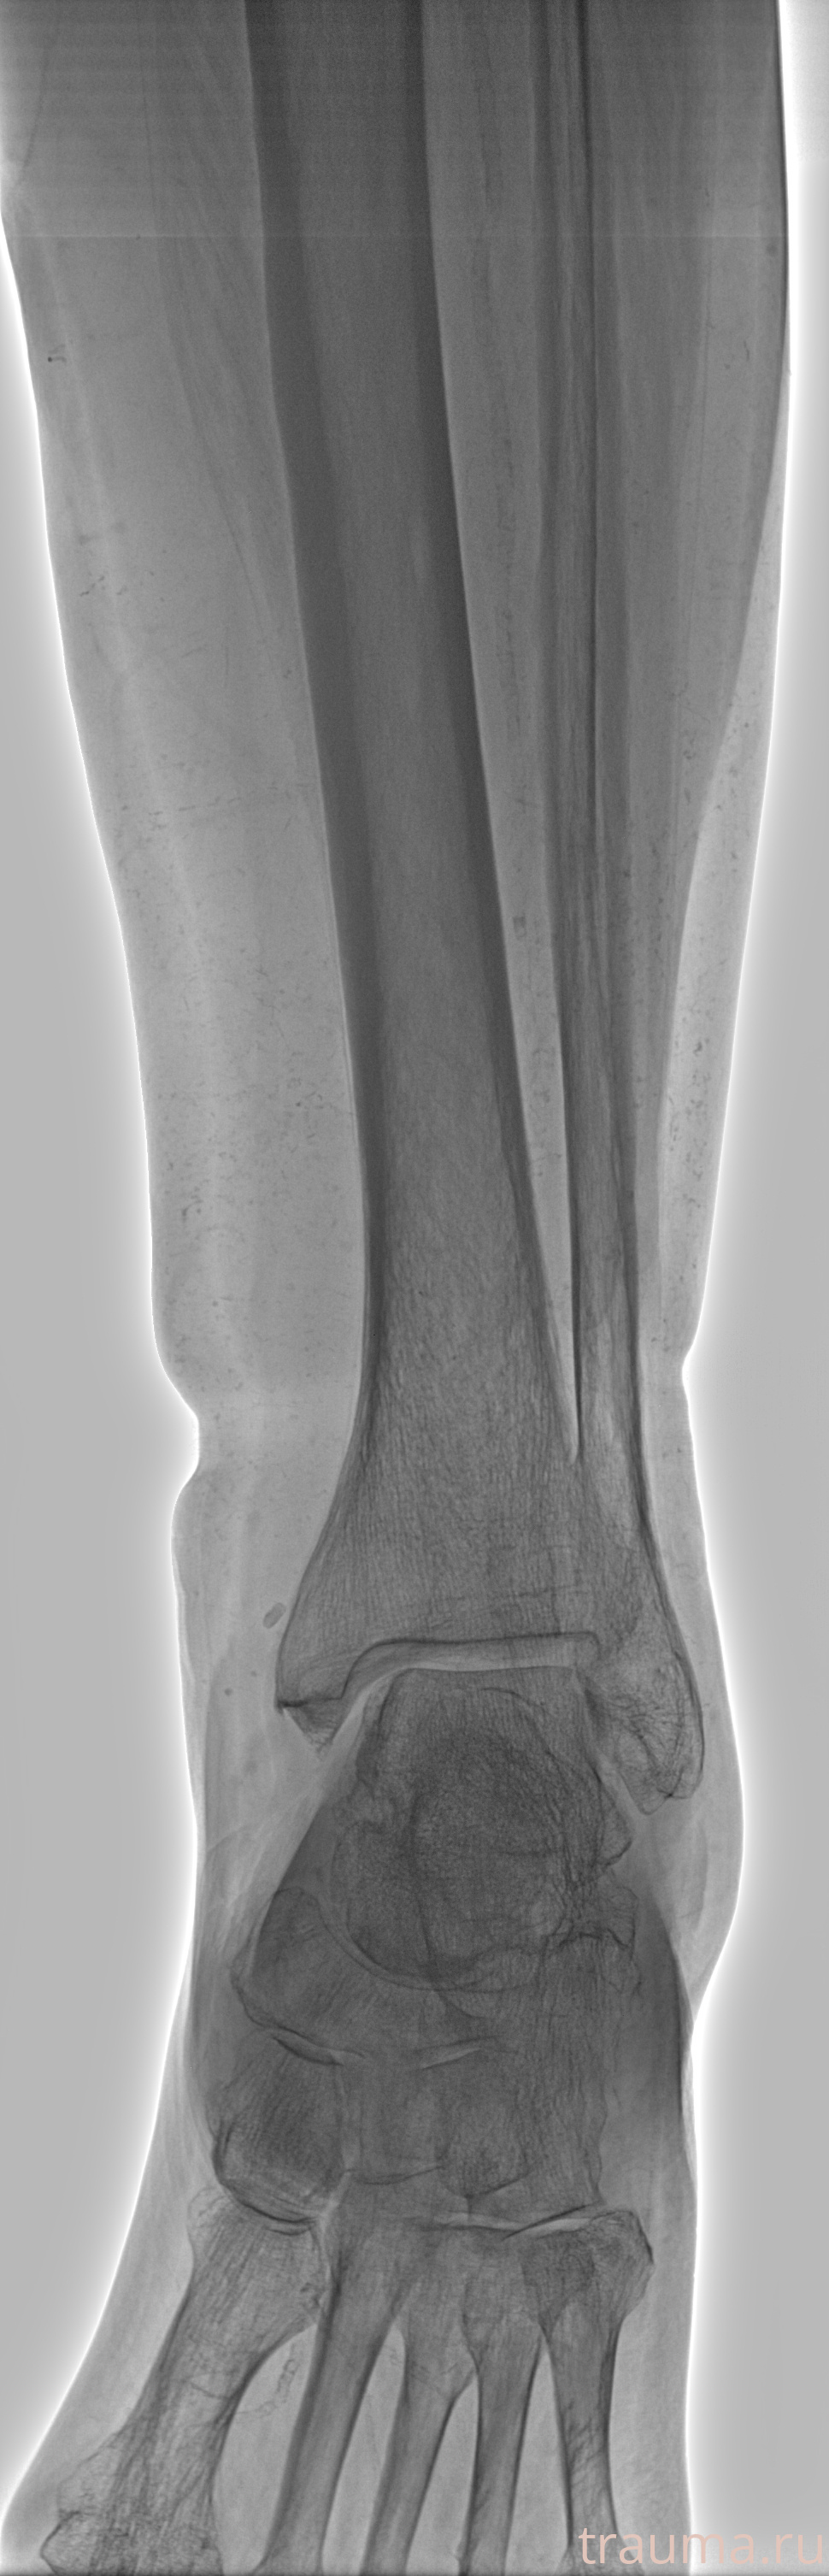

Рентгенограммы

Рентген на дому: по вашему адресу приезжает врач-рентгенолог, травматолог-ортопед с мобильным рентгеновским аппаратом, проводит диагностику травмы или заболевания, делает необходимые рентгенограммы, дает рекомендации по дальнейшему лечению. Получить качественные снимки в домашних условиях возможно благодаря уникальной методике, разработанной МосРентген Центром для института  Склифосовского